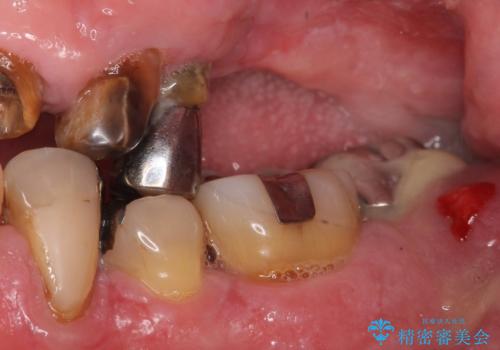

- 歯がぐらぐらで咬めないことを主訴に来院された患者様です。

他院では上顎骨が薄いためインプラントできないと言われたとのことでした。

精査したところ、歯周病に罹患した歯を長年放置したことから骨吸収が進行し、上顎骨の厚みはとても薄くなっていました。

全顎的な歯周病治療を行ったのち、上顎洞底挙上術(上顎骨に骨を増やす手術)を併用したインプラント埋入を行いました。